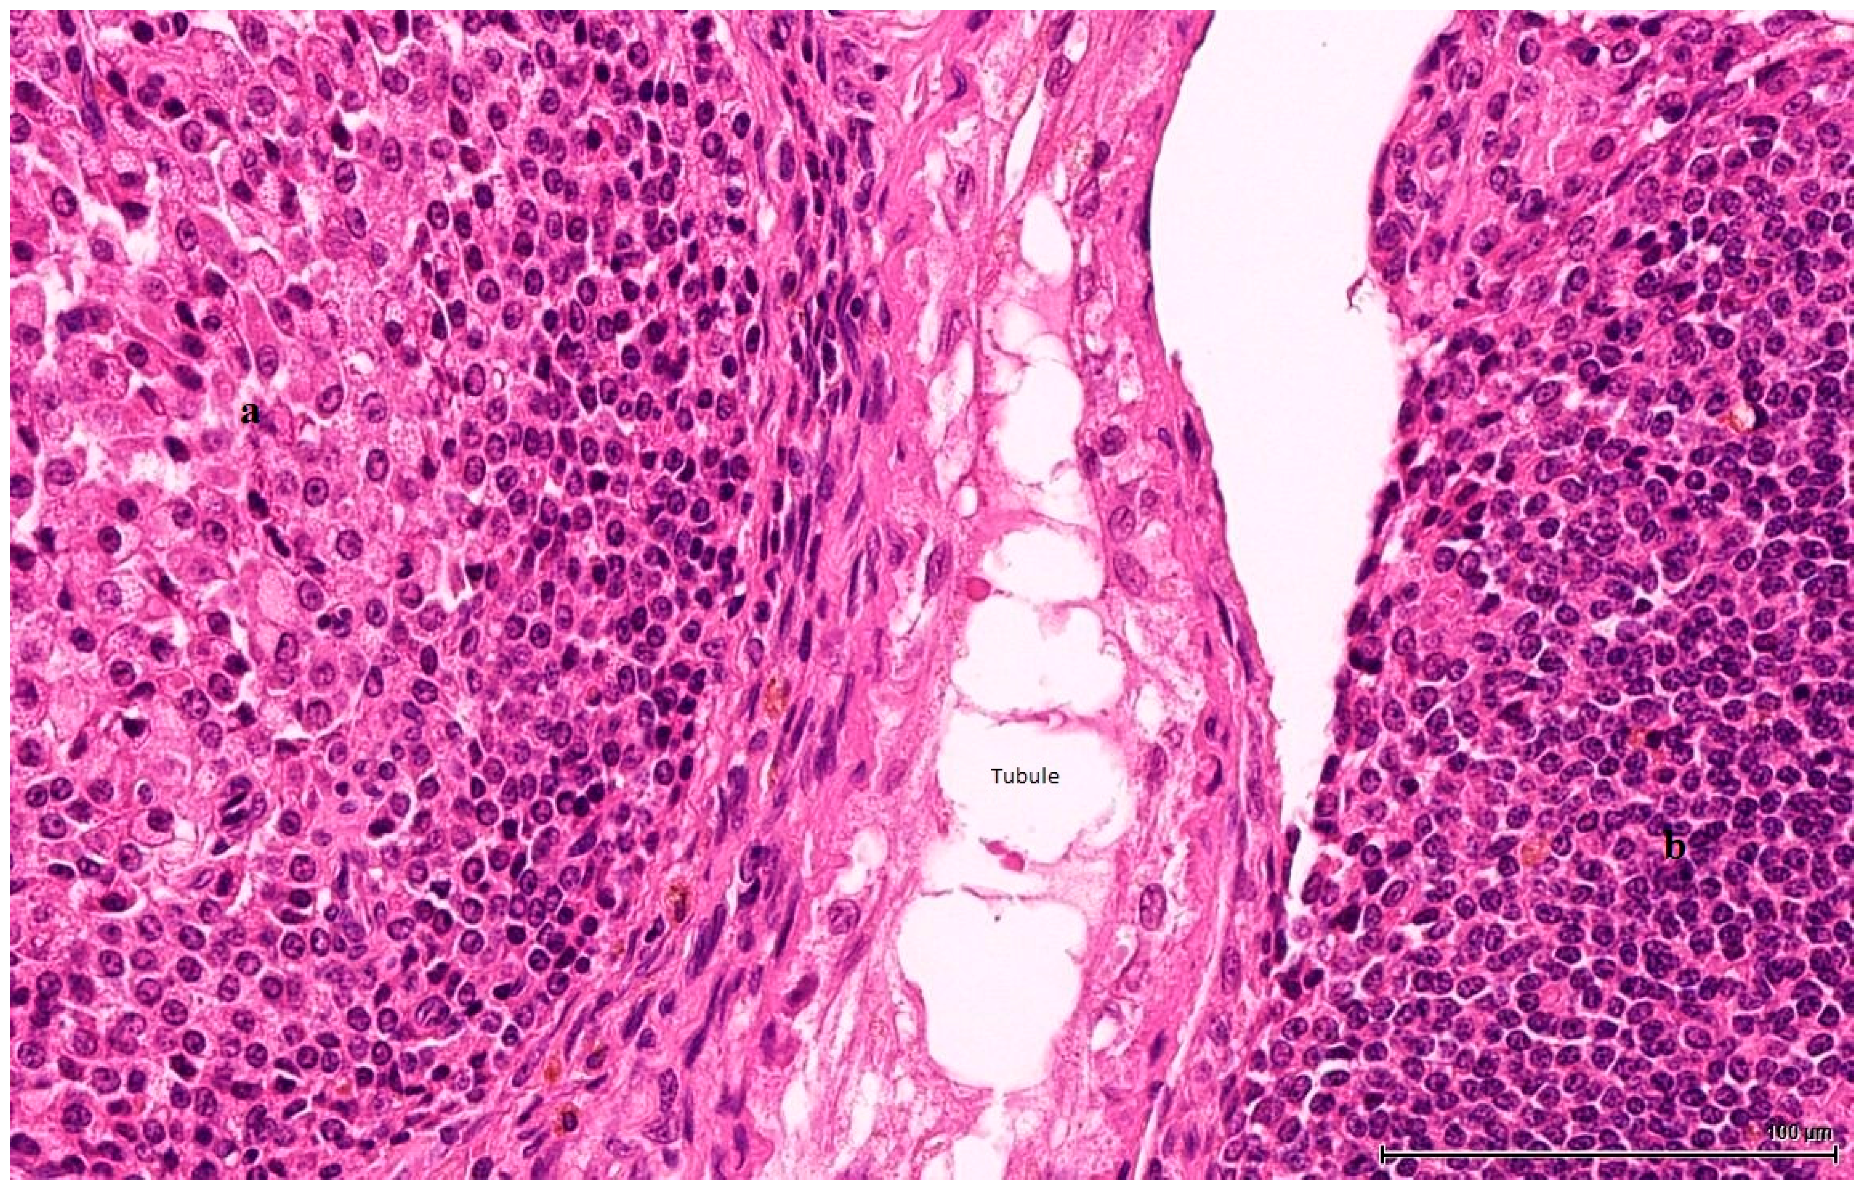

Figure 3. OTA-treated Case 2. Two cell populations of LCT. On the left side: larger cells, with eosinophilic and foamy cytoplasm (a) and on the right small cells with basophilic appearance (b), mimicking a lymphoid infiltrate. In between, an atrophic seminiferous tubule (H&E).

These are nodular cellular proliferations, usually multinodular, frequently coalescent nodules, usually solid with cystic spaces (empty or filled with proteinaceous material), composed of sheets of large, polyhedral cells with abundant eosinophilic cytoplasm, which is frequently lipidized. The nuclei are uniform, round, with evenly distributed chromatin and occasional small nucleoli; some are mitotically active. Admixed with these large cells are smaller ones, with little, unremarkable cytoplasm and small hyperchromatic nuclei. These two cell populations can form separate individual nodules, or they can intermingle, with no sharp demarcation, as there seems to be an imperceptible transition from one to the other. The large, clear cells with foamy, micro- and macrovesicular cytoplasm contain lipid vacuoles and sometimes golden brown lipofuscin pigment identified as purple red on a PAS stain (Figure 2). The small cell type has a basophilic appearance, mimicking a lymphoid infiltrate (Figure 3). The stroma is scant and occasionally hyalinised, with a rich vascular network; extensive haemorrhaging is present in some cases.